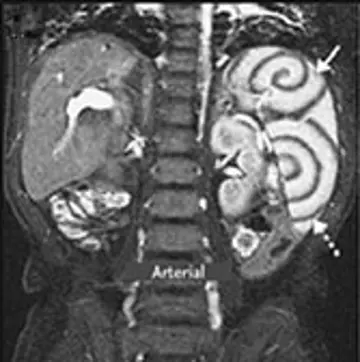

مارپیچ‌های طحال